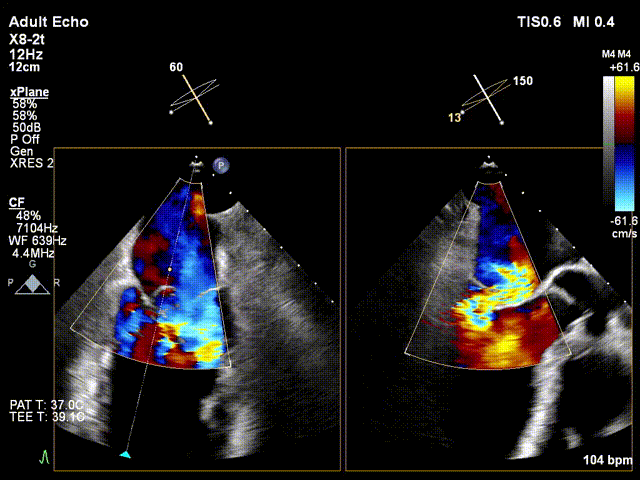

TEE显示,二尖瓣夹植入后反流减少

图片

3D TEE显示,双孔化形成良好